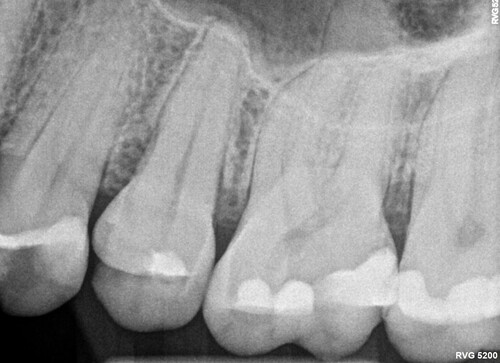

1. Zdjęcie punktowe to precyzyjne badanie radiologiczne pojedynczego zęba i jego okolicy. Umożliwia dokładną ocenę korzeni, kości oraz zmian zapalnych, pomagając w postawieniu trafnej diagnozy i zaplanowaniu leczenia. Prześwietlenie zęba najczęściej wykonuje się przed leczeniem kanałowym lub ekstrakcją.